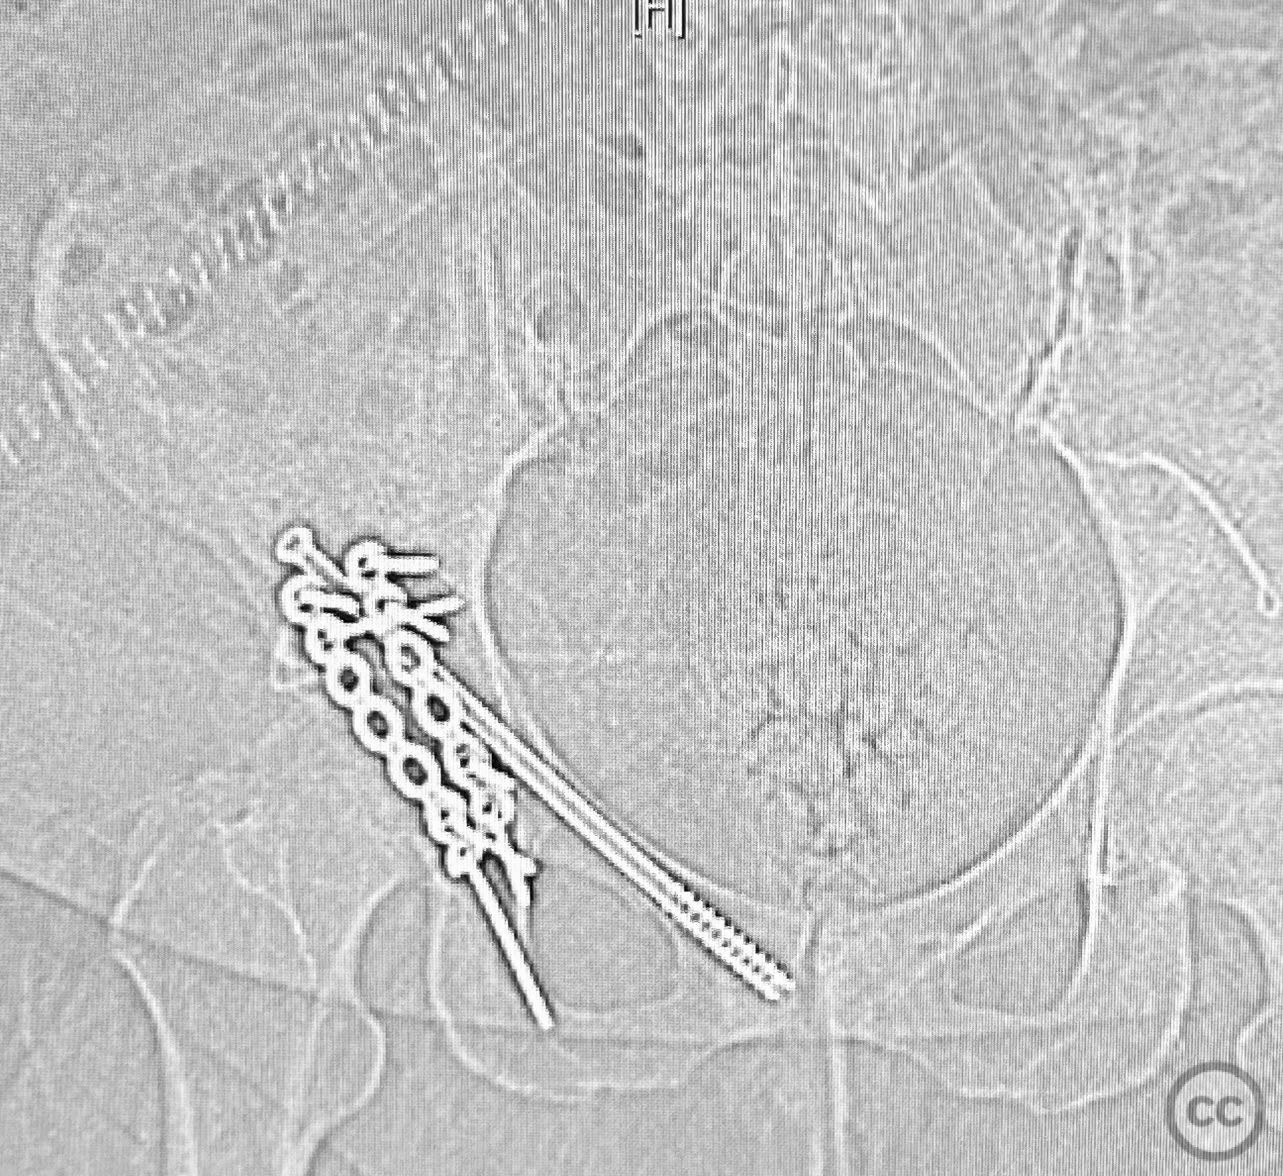

The transverse fracture was manipulated and temporarily stabilized using a reduction clamp applied across the fracture plane. Under biplanar fluoroscopic guidance, a cannulated cancellous lag screw was percutaneously inserted to achieve interfragmentary compression across the transverse component. The reduction clamp was then removed. Posterior wall fragments were anatomically reduced and stabilized with contoured buttress plates spanning both the posterior wall and providing additional stabilization to the transverse component. Postoperative CT confirmed satisfactory reduction and fixation of both acetabular columns and restoration of articular congruity.